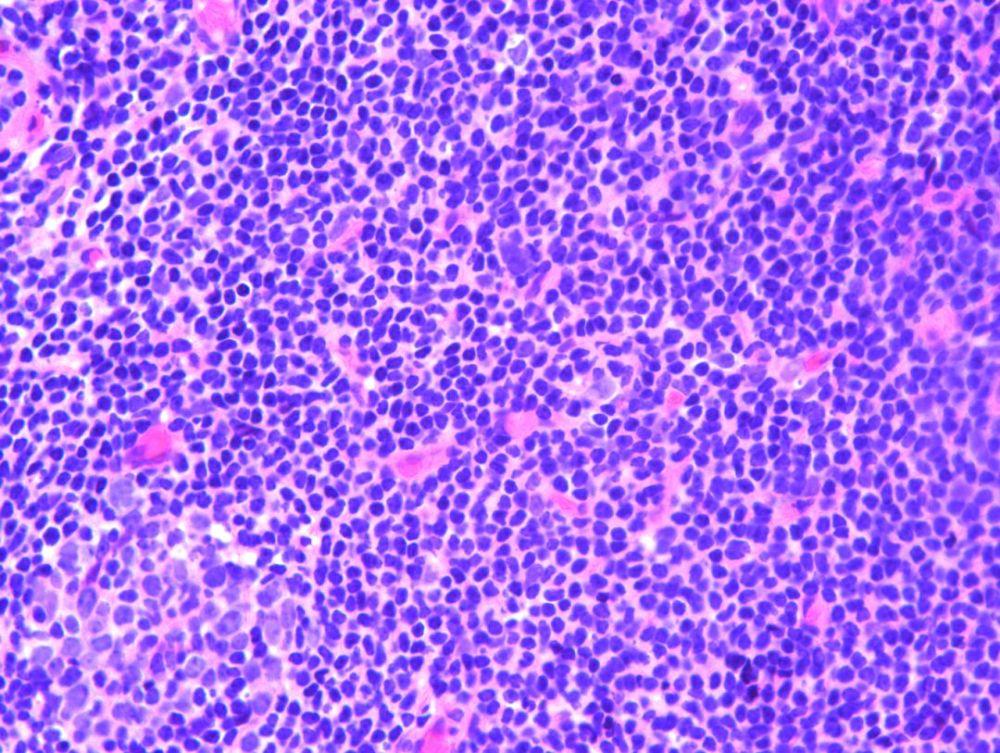

急性舞蹈病没有并发症,很少死亡,所以病理资料也很少。而散在性动脉炎及大脑皮层、基底核、黑质、丘脑下核、小脑齿状核神经细胞变性是本病的主要病理改变。偶见点状出血,有时可见小的栓塞性梗塞。脑软膜有轻微的炎症变化,血管周围淋巴细胞浸润。